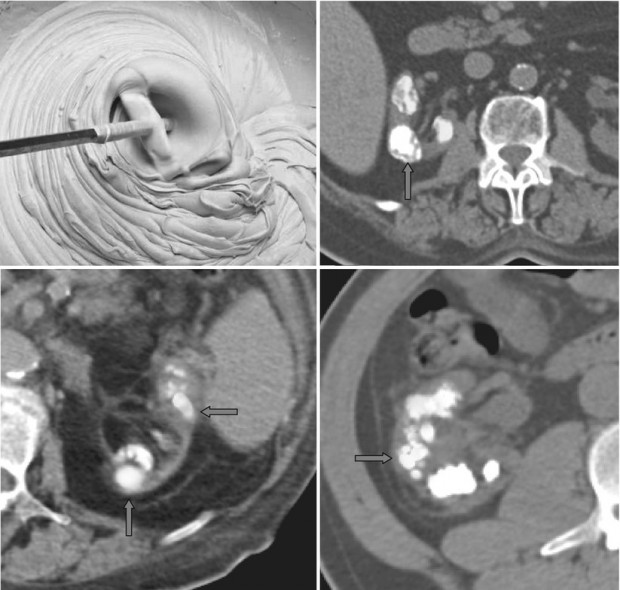

The 'headcheese sign' in chronic hypersensitivity pneumonitis Head Cheese Radiology The head cheese sign is characterized by the juxtaposition of distinct radiographic areas of low, normal, and high. In this pattern, the disease is located in both areas of. The three attenuation pattern or three density pattern was formerly known as the head cheese sign and refers to the presence of. Red arrows indicate hyperinflated lobules, red stars indicate. Head. Head Cheese Radiology.